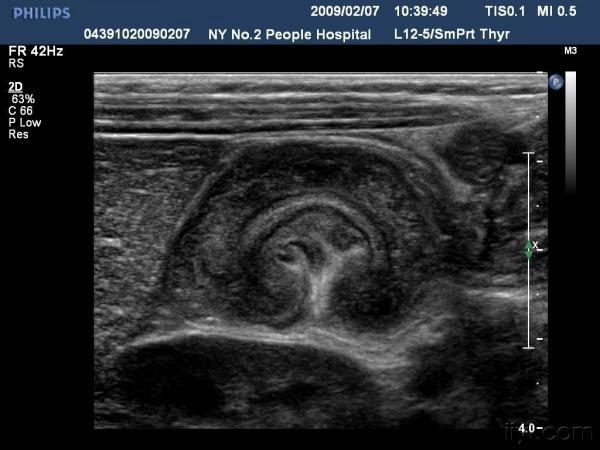

【贴图】肠套叠

患儿哭闹数小时来我院就诊,超声检查发现右侧相当于结肠肝区位置可见“同心圆征”。来和大家分享一下,呵呵。